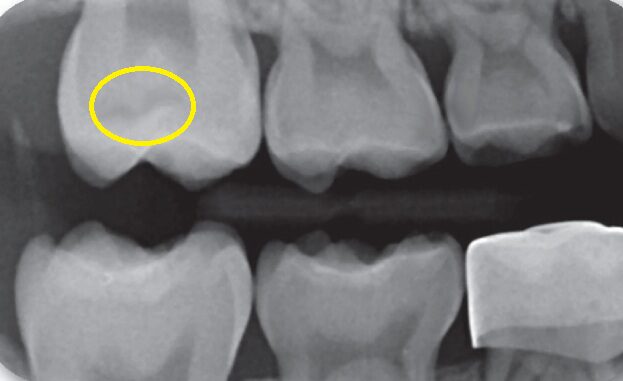

Radiographic Findings

Radiographic bitewing image shows occlusal recurrent caries under the sealants, now requiring further restorative work. It’s a reminder that sealants should live in the grooves, not on the mountain slopes. When bulk increases, so does the risk of wear, fracture, and marginal breakdown, all perfect entry points for bacteria.